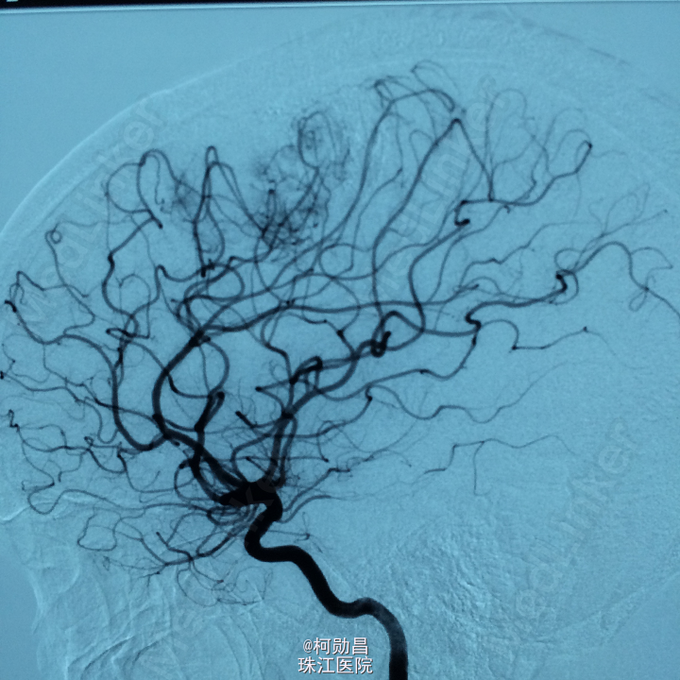

诊断:左侧顶叶占位 处理:行DSA检查,提示肿瘤染色,予PVA颗粒行血管内栓塞治疗。

术后再予开颅手术治疗,书中见供血动脉闭塞,出血量少。